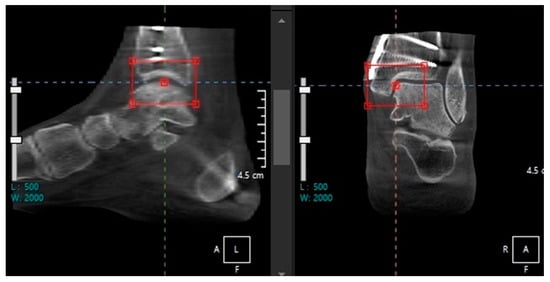

Ankle Replacement Surgery